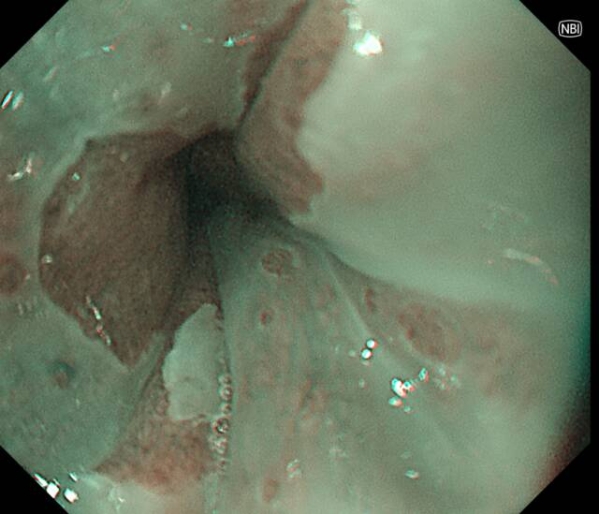

患者李先生(化名),60多岁,平日不抽烟不喝酒,无任何消化道症状,但有家族史,在子女的带领下来做胃肠镜精查。前两年刚做过胃肠镜,未发现异常。在新镜界精查中,发现胃角处有一黏膜与正常略微不同,经NBI+放大内镜放大观查,考虑胃早癌,活检证实为高级别上皮内瘤变。恰逢麻兴华教授(新镜界日方特聘专家)来院坐诊,于是由麻教授带领内镜团队行内镜下黏膜剥离术(ESD),术后患者痊愈。

因为是早期胃癌,在内镜下行黏膜剥离术(ESD),就能够治愈,无需外科手术及放化疗。这是不幸中的万幸,患者今后只需定期胃镜复查即可。